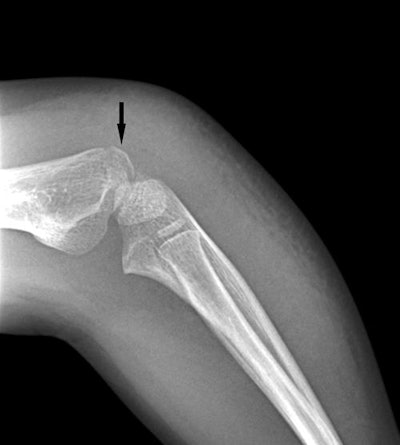

Four-year-old girl with a nondisplaced lateral condylar fracture. Above, x-ray performed by a pediatrician at a freestanding pediatric urgent care center with nonorthogonal positioning of the left elbow, showing possible lateral condylar fracture, but only on one image (arrow). Beam collimation was not used, leading to unnecessary radiation to the majority of the forearm. The patient was sent to the main hospital for additional imaging; with proper orthogonal positioning and collimation performed by a technologist, the fracture is delineated (below, arrow) and the diagnosis made with greater confidence. Images courtesy of Dr. J. Herman Kan.

Four-year-old girl with a nondisplaced lateral condylar fracture. Above, x-ray performed by a pediatrician at a freestanding pediatric urgent care center with nonorthogonal positioning of the left elbow, showing possible lateral condylar fracture, but only on one image (arrow). Beam collimation was not used, leading to unnecessary radiation to the majority of the forearm. The patient was sent to the main hospital for additional imaging; with proper orthogonal positioning and collimation performed by a technologist, the fracture is delineated (below, arrow) and the diagnosis made with greater confidence. Images courtesy of Dr. J. Herman Kan.Quality assurance